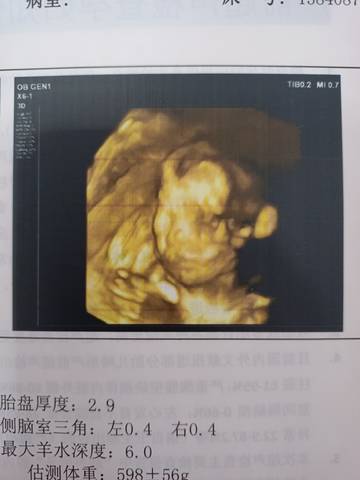

4维单子能看出男宝女宝吗

journal_insert_pic_1688226809journal_insert_pic_1688226839